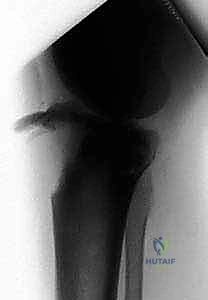

2. التصوير بالأشعة السينية (X-Rays)

هو الخطوة التشخيصية الأساسية. يتم أخذ صور من زوايا متعددة (أمامية خلفية AP، وجانبية Lateral). الصورة الجانبية هي الأكثر أهمية لأنها تظهر بوضوح مدى انفصال (انزياح) حدبة الظنبوب عن مكانها الطبيعي، وتظهر أيضاً ارتفاع الرضفة (Patella Alta).